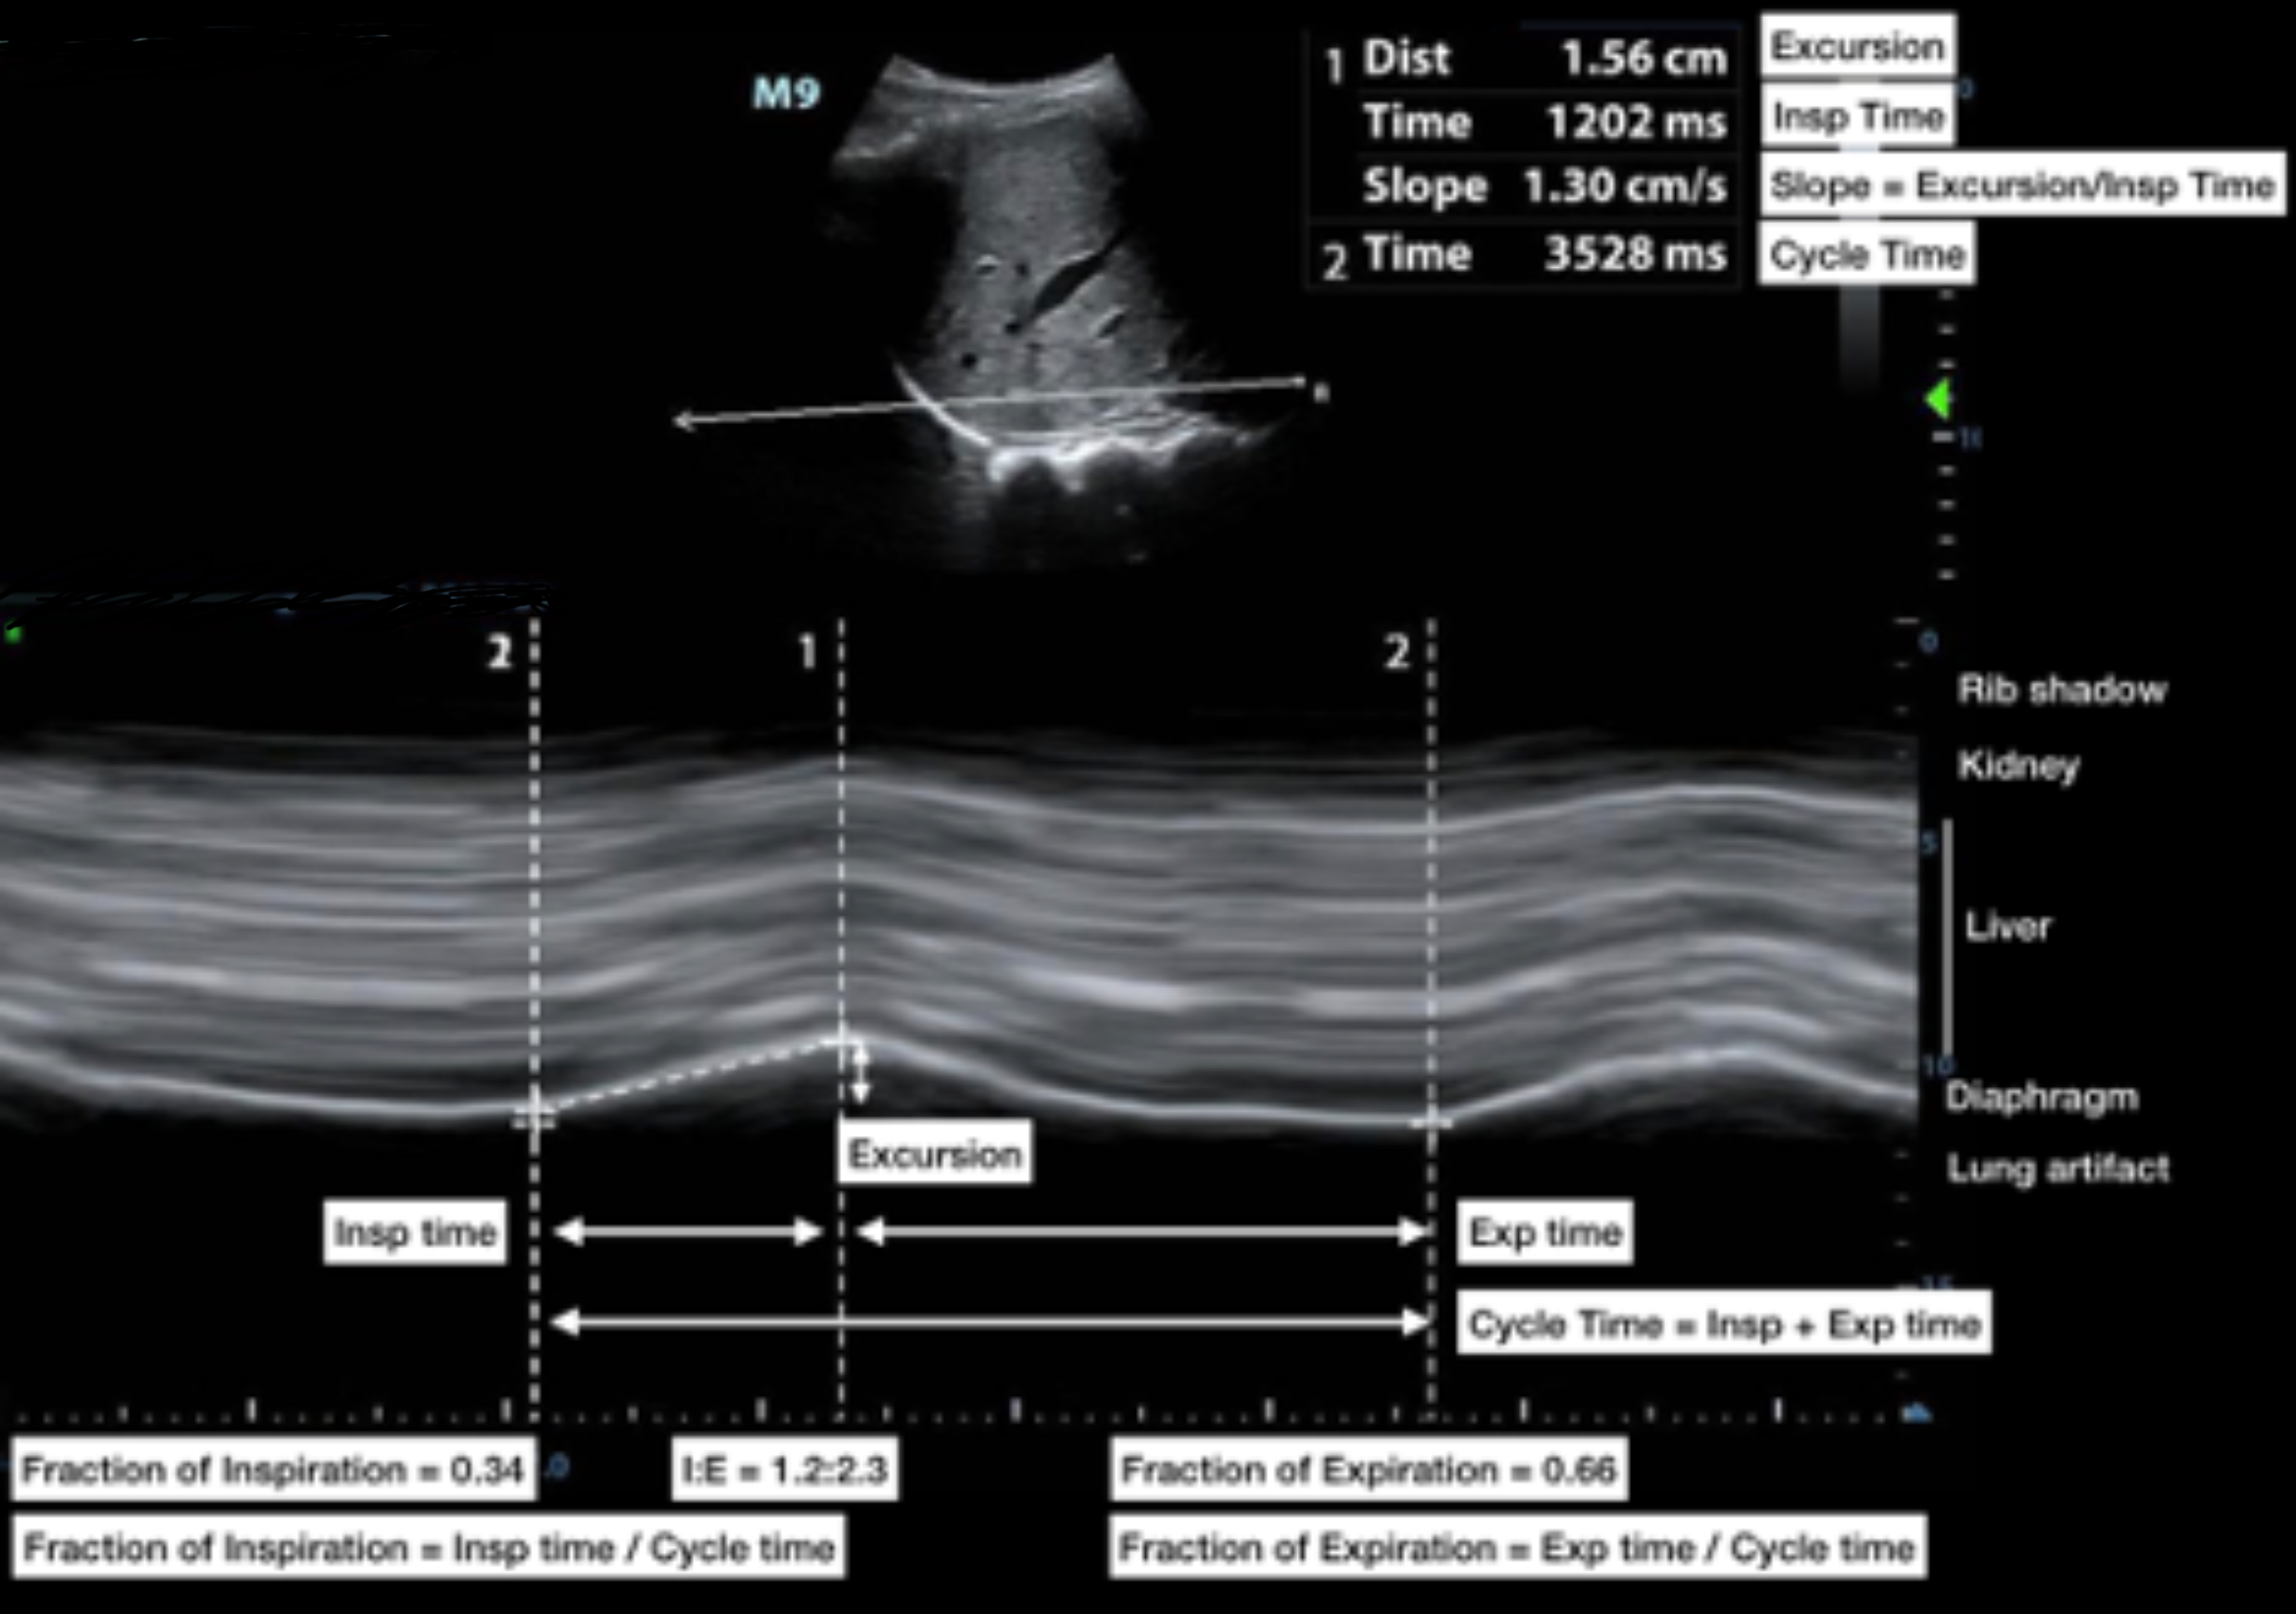

Cureus The Use of AngleIndependent MMode in the Evaluation of Diaphragmatic Excursion Du Web diaphragmatic excursion (de) was calculated as the difference between axial slices through the lungs on. The diaphragmatic excursion (de), which. Web diaphragmatic excursion is a quantitative measure of expiratory effort as validated by both lung and tracheal. The diaphragm, the main muscle of respiration, is comprised of a dome. Web ultrasound assessment of diaphragmatic excursion is an easy, noninvasive,. Diaphragmatic Excursion Du.

Cureus The Use of AngleIndependent MMode in the Evaluation of Diaphragmatic Excursion Du Web diaphragmatic excursion (de) was calculated as the difference between axial slices through the lungs on. The diaphragm, the main muscle of respiration, is comprised of a dome. Web functional anatomy of the diaphragm. The diaphragmatic excursion (de), which. Web measurement of diaphragmatic excursion and diaphragmatic thickening fraction predict the probability of. Web there are two diaphragm sonographic predictors of. Diaphragmatic Excursion Du.

Image demonstrating measurement of the diaphragmatic inspiratory Diaphragmatic Excursion Du Web measurement of diaphragmatic excursion and diaphragmatic thickening fraction predict the probability of. Web diaphragmatic excursion (de) was calculated as the difference between axial slices through the lungs on. The diaphragmatic excursion (de), which. The diaphragm, the main muscle of respiration, is comprised of a dome. Web there are two diaphragm sonographic predictors of weaning outcome: Web ultrasound assessment of. Diaphragmatic Excursion Du.

Measurements of the diaphragmatic excursion (DE) and systolic velocity Diaphragmatic Excursion Du Web diaphragmatic excursion (de) was calculated as the difference between axial slices through the lungs on. The diaphragmatic excursion (de), which. Web diaphragmatic excursion is a quantitative measure of expiratory effort as validated by both lung and tracheal. Web functional anatomy of the diaphragm. Web there are two diaphragm sonographic predictors of weaning outcome: Web ultrasound assessment of diaphragmatic excursion. Diaphragmatic Excursion Du.

Diaphragmatic excursion (DE) measurement. a Bmode diaphragmatic Diaphragmatic Excursion Du Web measurement of diaphragmatic excursion and diaphragmatic thickening fraction predict the probability of. The diaphragmatic excursion (de), which. Web there are two diaphragm sonographic predictors of weaning outcome: Web diaphragmatic excursion is a quantitative measure of expiratory effort as validated by both lung and tracheal. The diaphragm, the main muscle of respiration, is comprised of a dome. Web functional anatomy. Diaphragmatic Excursion Du.